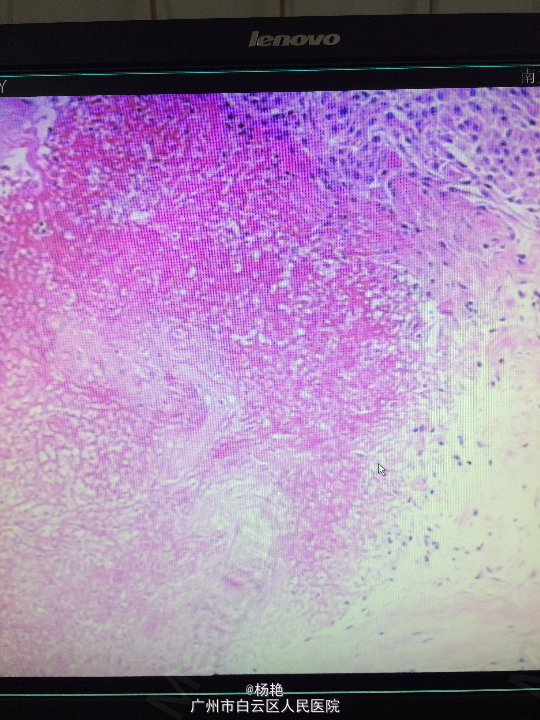

诊断:左额叶脑膜瘤 处理:在静脉全麻下行左侧额底脑膜瘤切除术,术后病理提示:脑膜瘤